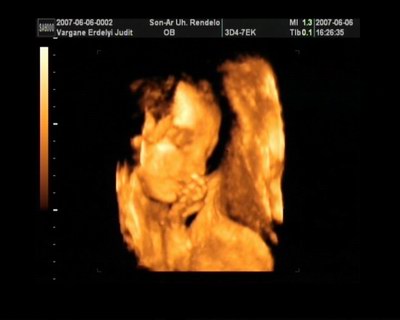

Melcsi! Nagyon határozott arcocskája van a fiadnak, karakteres, gyönyörű kispasas!

Gratulálok és nagyon köszönöm a képeket!